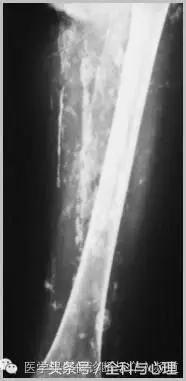

4、痛风石

为尿酸盐沉积形成,发生在关节周围软组织、包括韧带、肌腱、滑囊,眼、耳、鼻、喉、皮肤, 50%的钙化为X线平片可见。

痛风石,可见软组织肿胀及钙化灶。